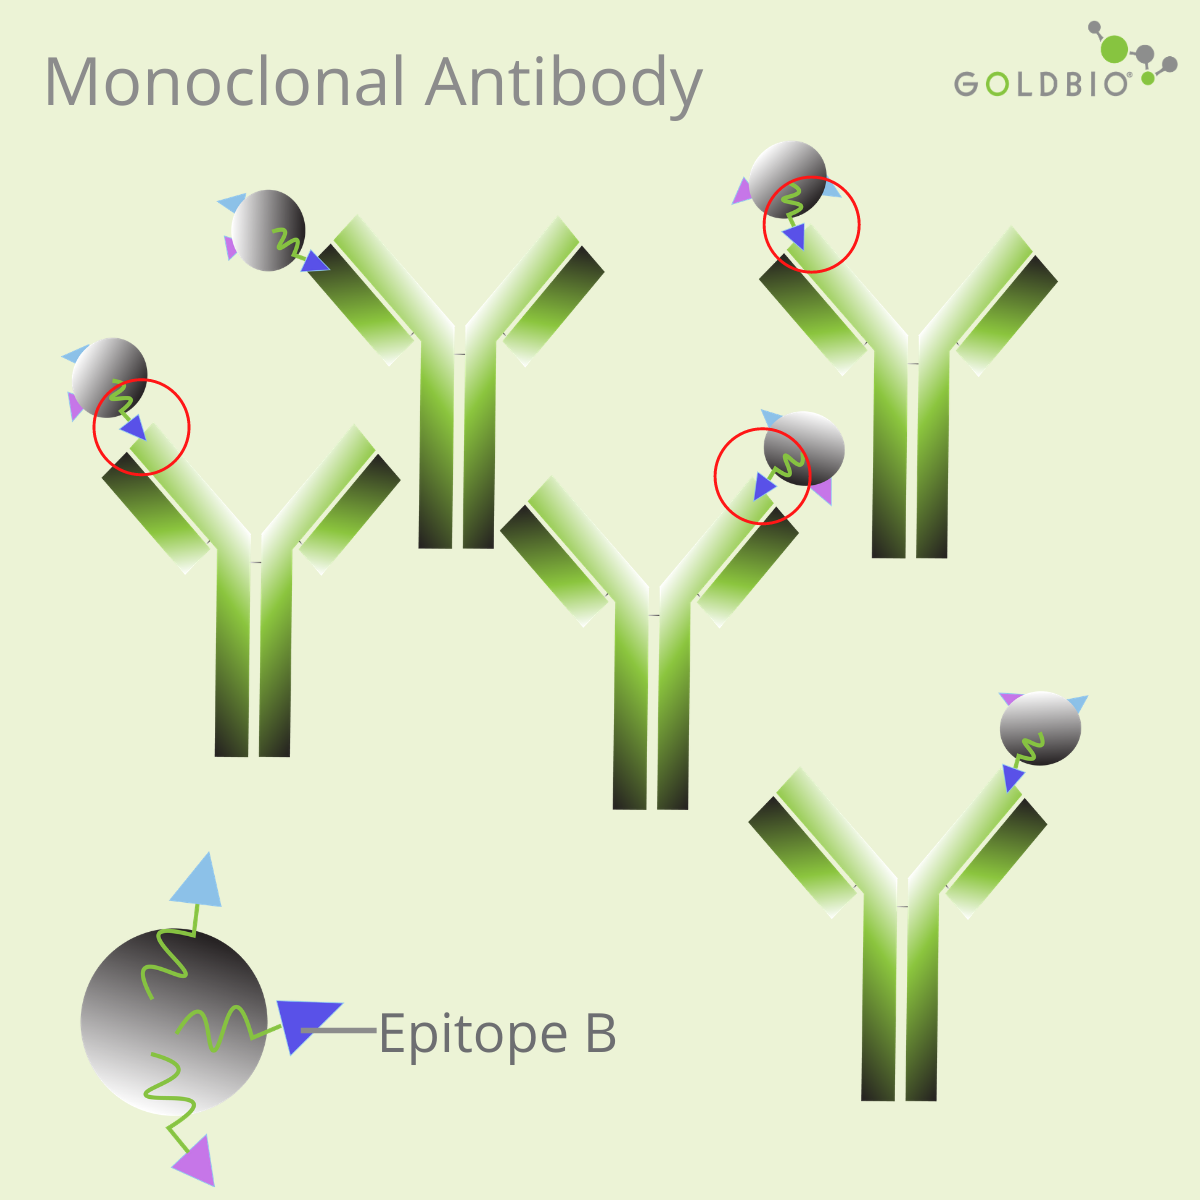

In protein research, there are two popular types of antibodies: monoclonal antibodies and polyclonal antibodies.

Monoclonal antibodies have high specificity, so they are useful for some research applications requiring antibodies specific to a single epitope. Due to this reason, producing therapeutic antibodies is one attractive approach for drug development (Lu et al., 2020).

Monoclonal antibodies are also useful for quantifying the levels of a particular target protein; for example, in ELISA or radioimmunoassay.

They can also be used for Western Blotting (WB), immunohistochemistry (IHC), and immunofluorescence assay (IF). However, depending on the epitope, monoclonal antibodies can also be ineffective for these methods. A change in the structure of protein caused by chemicals, pH, or temperature, can affect the efficiency of the monoclonal antibodies.

Monoclonal antibodies produced against native proteins may recognize a conformational epitope, or an epitope containing discontinuous amino acid residues (Liang, 1998). As a result, these monoclonal antibodies may fail to recognize the epitope on the denatured state of the target proteins.

Discontinuous residues are amino acids far apart in primary sequences, but close to each other in the folded structures. In this case, choose a monoclonal antibody that can recognize continuous residues, or linear epitopes. Otherwise, consider to use a polyclonal antibody.